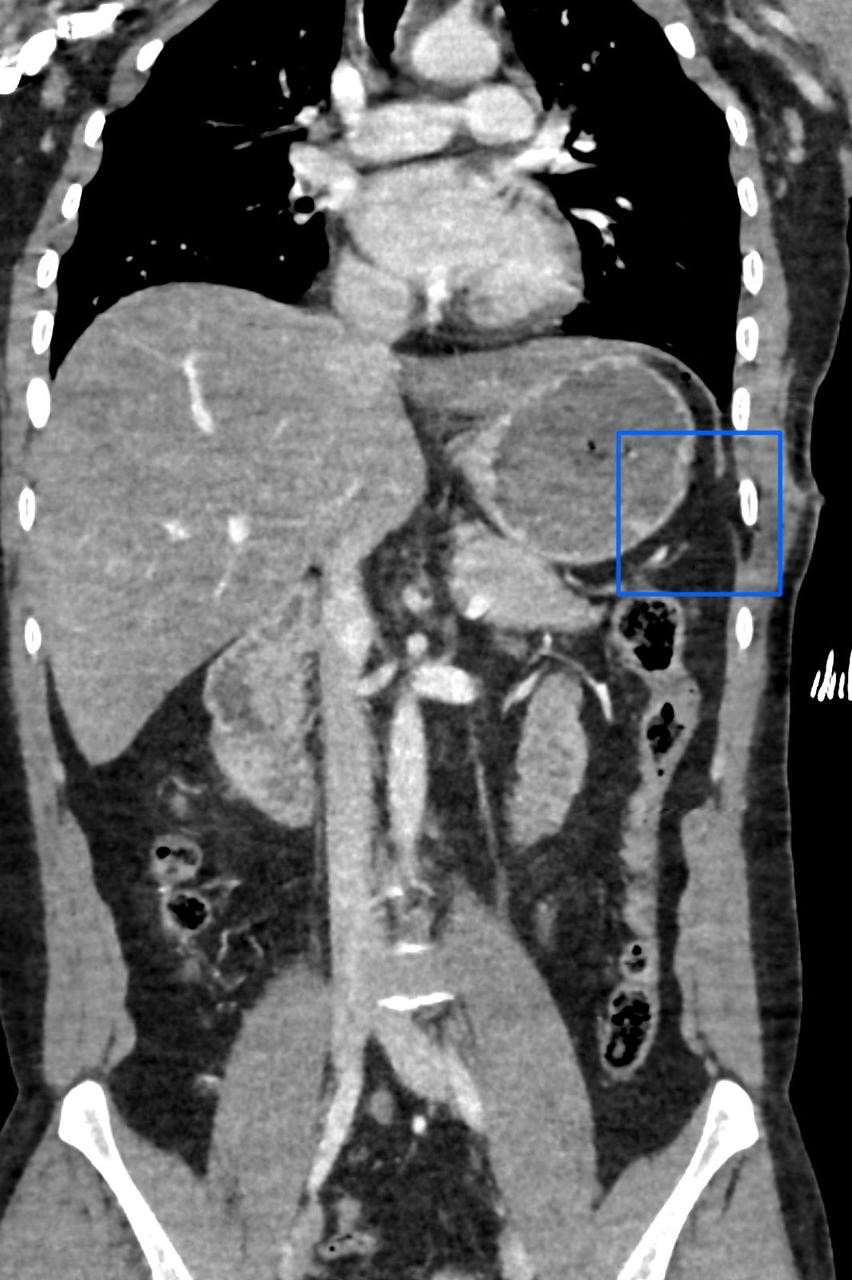

تمكن مستشفى الإيمان العام عضو تجمع الرياض الصحي الأول من إنقاذ حياة شاب عشريني تعرض لإصابة في الجهة اليسرى من الصدر؛ أدت إلى حدوث قطع في الحجاب الحاجز، وثقب في القولون المستعرض.

حيث قام الفريق الطبي بقيادة رئيس قسم الجراحة العامة استشاري الجراحة والمناظير د. سعد الدوسري، واستشاري الجراحة العامة د. ريان الحوشان بإجراء جراحي عاجل تم خلاله إصلاح الإصابات المذكورة عن طريق المنظار الجراحي عبر ثلاثة فتحات صغيرة بحجم 5 مم، تكللت بالنجاح -ولله الحمد-.

الجدير بالذكر أن مثل هذه الإصابات عادة يتم إجراؤها عن طريق الشق الكامل للبطن، ولكن إستطاع الفريق الطبي بمستشفى الإيمان العام تفاديه -بتوفيق من الله-؛ حيث ساهمت خبرة الفريق الطبي وتوفر الإمكانيات والتقنيات الحديثة في المستشفى من إجراء العملية وفق أفضل الممارسات الطبية والتي ساهمت بتحسن حالة المريض في فترة وجيزة -ولله الحمد-.